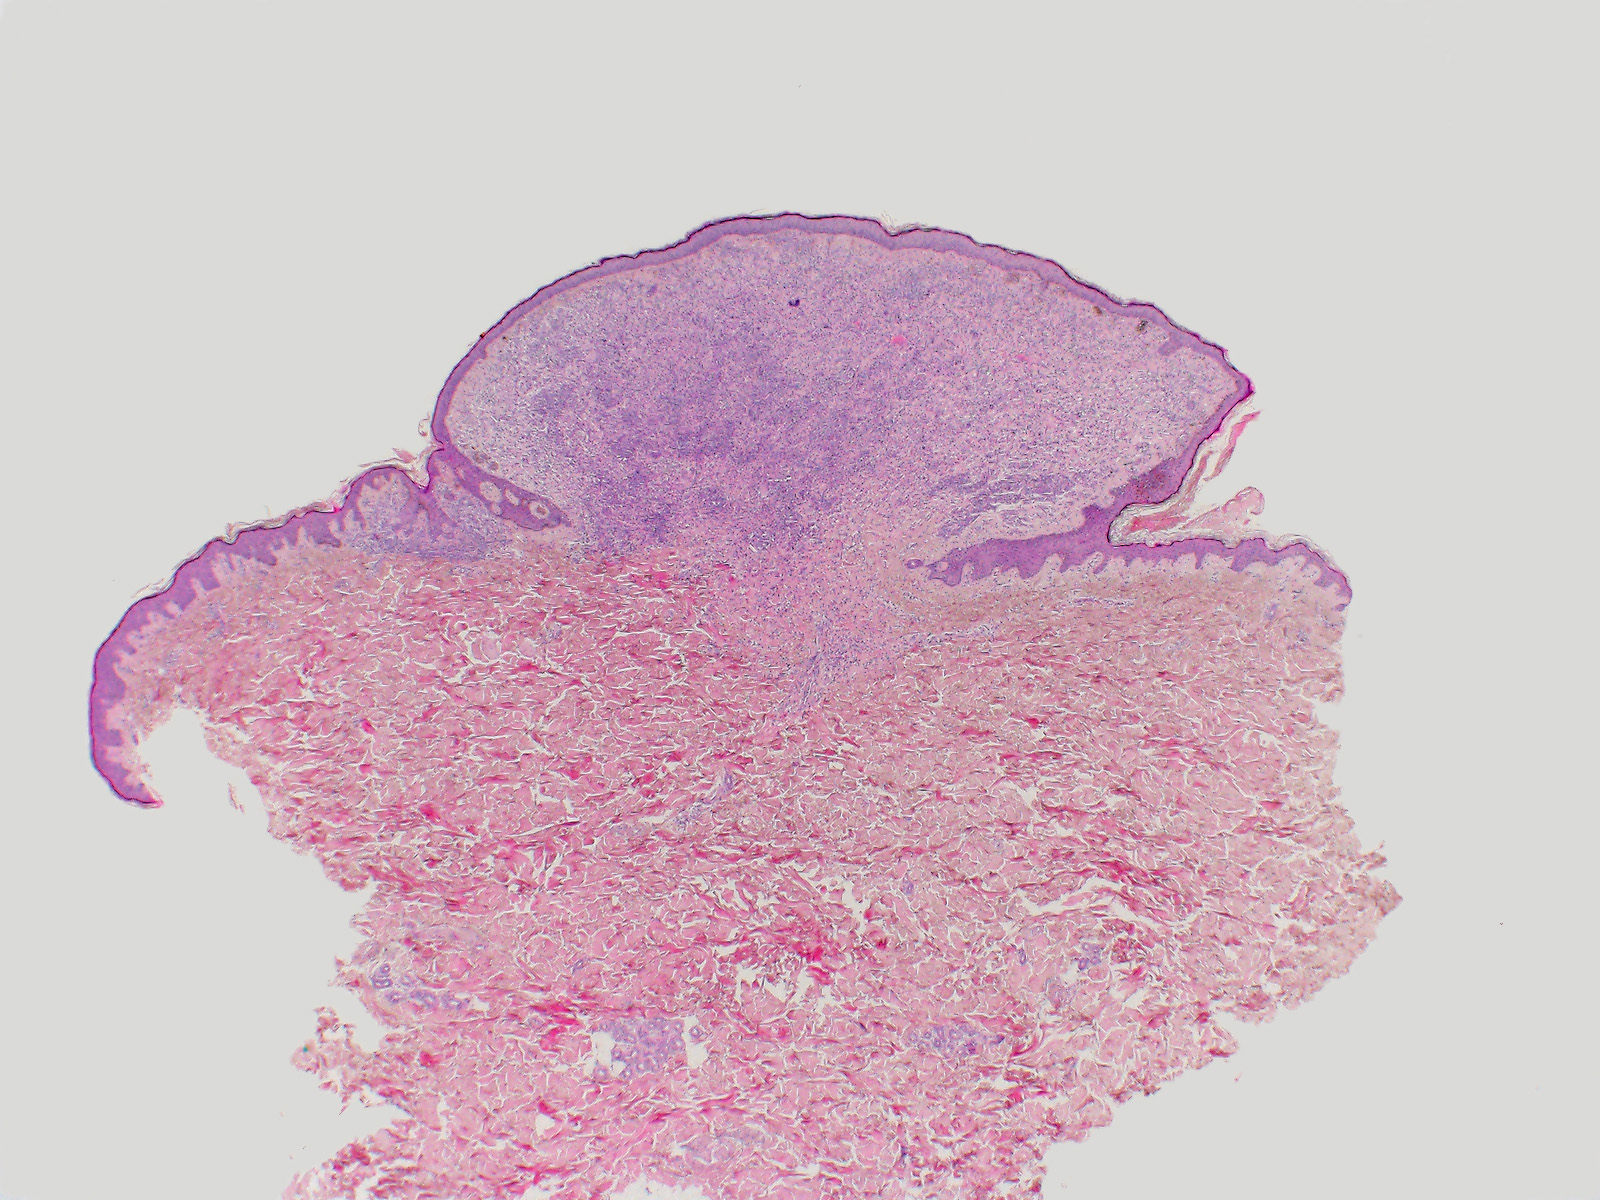

Wiesner Naevus

benigner Tumor

Haut, Rumpf

Haut

Polypoider, symmetrischer, überwiegend intradermaler Naevus mit Kollarettenbildung der Epidermis.

Die grossen epitheloiden Zellproliferate zeigen einen Verlust der BAP1 Expression im Zellkern. Die Zellkerne des gewöhnlichen Naevusanteils sind positiv. Beide Komponenten sind immunhistochemisch positiv für die BRAF V600E Mutation.

Papillomatöser Naevus am Rücken einer 21 jährigen Patientin.

In Wiesner's nevu, classic features of Spitz nevus, such as Kamino bodies, spindle-shaped melanocytes, epidermal hyperplasia and clefting around junctional melanocytic nests, are absent. These tumors may be sporadic or appear multiple in patients with an autosomal dominant syndrome caused by germline mutations in BAP1. Both sporadic and Wiesner nevi in the familial syndrome show BRAF V600E mutation and loss of nuclear staining for BAP1. If a BAP1 mutation is confirmed in a tumour, the patient's treating physician should be informed of the possibility of a BAP1 germline mutation, so they can consider whether genetic counselling and further testing of the patient and investigation of their family is appropriate. Wiesner's nevi may present as a pure large epithelioid cell proliferation or as in this case as a combined lesion in association with a conventional nevus. Pathology. 2013 Feb;45(2):116-26. Tumours associated with BAP1 mutations. Murali et al. Am J Surg Pathol. 2013 Feb;37(2):193-9. Combined BRAF(V600E)-positive melanocytic lesions with large epithelioid cells lacking BAP1 expression and conventional nevomelanocytes. Busam et al.